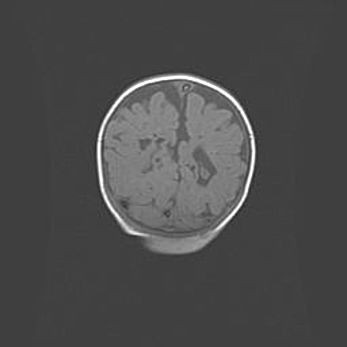

Сообщающаяся гидроцефалия. Кистозная энцефаломаляция головного мозга.

Возраст: 3 месяца 4 дня

Вес: 3100 г

Пол: женский

Окружность головы: 34 см

Срок гестации: 31 неделя

Кистозная энцефаломаляция головного мозга - одна из форм поражения головного мозга в детском возрасте. Характеризуется возникновением множественных и распространённых кист в коре, белом веществе и подкорковых образованиях головного мозга у плодов, новорождённых и детей раннего возраста. Развитие кистозной энцефаломаляции связано с внутриутробной асфиксией и гипотонией, родовой травмой, тромбозом синусов, пороками развития сосудов, инфекциями, сепсисом и другими причинами. Наиболее значимые инфекционные агенты: вирусы простого герпеса, цитомегалии, краснухи, токсоплазмы, энтеробактерии, золотистый стафилококк и другие.